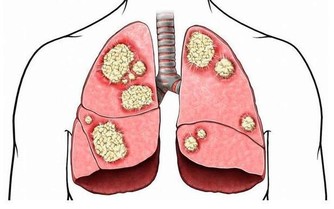

原發性肝癌是目前我國第4位常見惡性腫瘤及第2位腫瘤致死病因,嚴重威脅我國人民的生命和健康。

中華預防醫學會在《中國肝癌一級預防專家共識2018》中指出:國際癌症研究中心在進行全球惡性腫瘤負擔調查時發現,2012年全球新發肝癌病例高達78.2萬,死亡病例74.6萬,而其中50.5%的新發患者、51.3%的死亡患者都集中在中國。

更令人惋惜的是,目前中國的肝癌篩查推進工作很不理想,患者術後5年生存率也僅達12.1%,這更加突出了“肝癌防治”的必要性!而想要更有效地防治,了解肝癌的誘因,針對性地遠離危險因素則十分有必要。

肝癌的產生是肝臟長期、反复徘徊於修復和損傷之間,直到修復跟不上損傷就會發生腫瘤,一旦發生後果嚴重,所以一定要早預防、早發現、早治療。